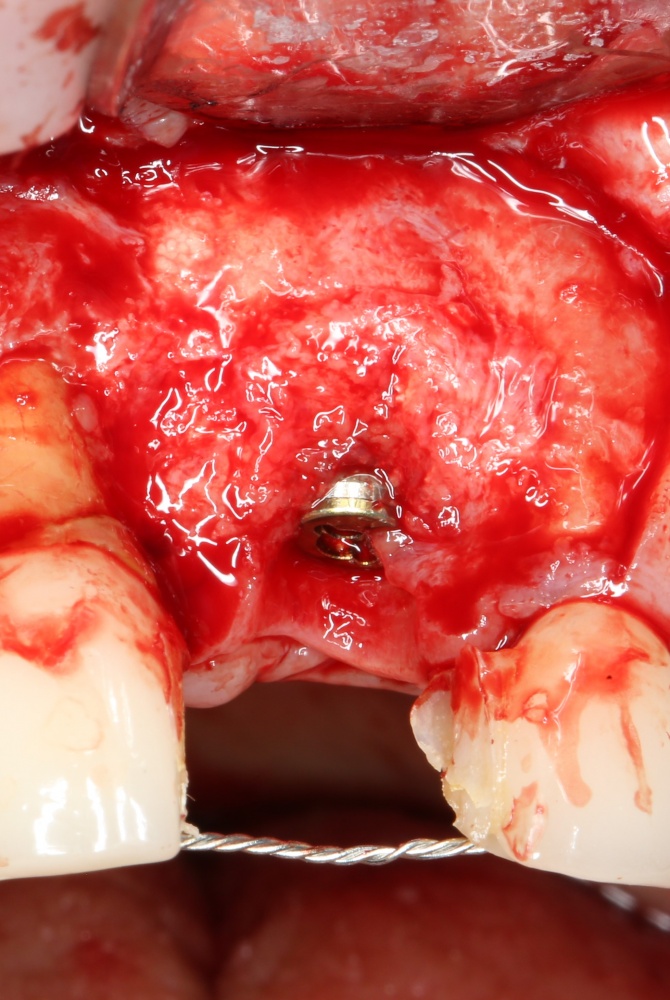

Рекомендации по установке имплантов. Для всех. Часть V.